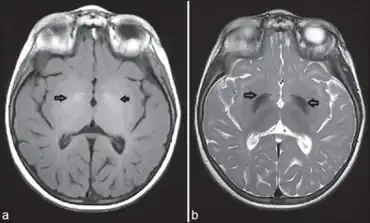

a) Bilateral globus pallidus hyperintensity b) bilateral globus pallidus hypointensity